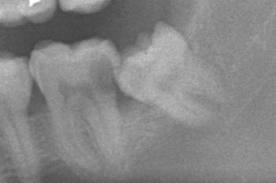

写真左下の親知らずが痛くなり抜歯しました。その後歯茎を除去して虫歯を露出させる処置を二回ほどしています。

レントゲンでは小さいですが、こう言う虫歯が一番怖いのです。

治療の成功率は極めて悪くすぐ再発しやすいのです。